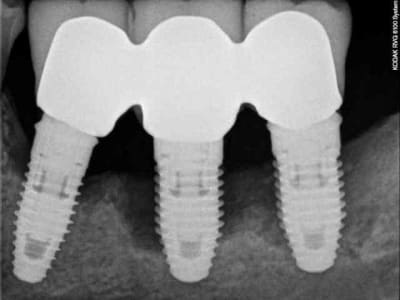

1 première consultation (septembre 2012)

2 rétro-alvéolaire (septembre 2012)

un an après !

ça s'arrange pas, voyez plutôt..

augmentation de la perte osseuse +++